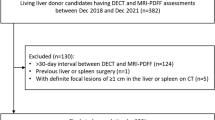

205 pairs of DECT and MRI PDFF performed within 30 days of each other occurred at our institution between 2016 and 2020. 33 pairs were excluded due to the presence of “fat–water swap” artifact in MR images [25]. In 44 cases, more than one pair of DECT and MRI were performed within a 30-day interval for the same patient; for these, the two closest exams were chosen (Fig. 1). The final study population included 128 unique pairs of CT and MRI examinations occurring in 128 patients (each patient had only one qualifying pair of examinations), with patient characteristics summarized in Table 1. 69/128 (54%) of patients were female. Mean age was 52 years (standard deviation 17 years, range 14–89 years). Nearly all patients’ CT examinations were performed in the emergency department (80%) or as inpatients (18%). In terms of the type of DECT scanner used, 102/128 (80%) of patients received “split beam” DECT, and 26/128 (20%) of patients received dual-source DECT. The vast majority of MRI examinations (90%) were performed in the inpatient setting (Fig. 2). The median time between CT and MRI examination was 2 days (range 0–28). The most common indication for MRI was pain (34/128, 26.5%), followed by known or suspected gallbladder/common bile duct stones (27/128, 21.1%) and abnormal liver function tests (24/128, 18.8%) (Table 2).